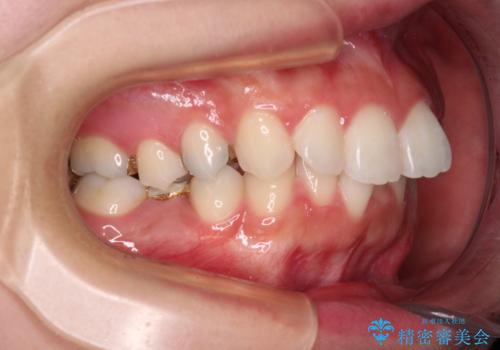

後方移動と同時上下歯列をワイヤー装置にて整え、奥歯の欠損部には矯正治療の途中でインプランを埋入していくこととしました。

上顎歯列全体を後方移動させたことで唇に当たる感覚は改善され、更には上下の正中位置も合わせることができました。